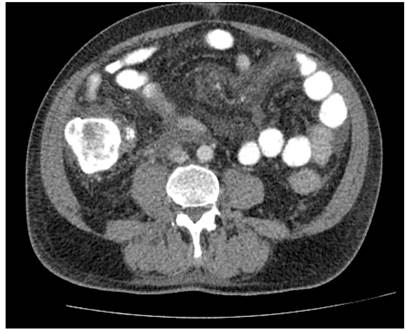

En hospital de remisión requirió manejo con apendicectomía laparoscópica y derivación de vía biliar por colangiopancreatografía retrógrada endoscópica, con inserción de un stent biliar. Hallazgo intraquirúrgico de un plastrón apendicular, abundante líquido peritoneal cetrino, estrechez del conducto hepático común, con sospecha de compromiso neoplásico. Se trasladó al Hospital Militar Central en Bogotá, Colombia, para continuar con manejo integral. Se documentó síndrome biliar obstructivo, con recuento de bilirrubina total de 3,02 mg/dL, bilirrubina directa de 2,71 mg/dL, fosfatasa alcalina de 1006 UI/L, alanina aminotransferasa (ALT) de 149 U/L y aspartato aminotransferasa (AST) de 139 U/L. Los hallazgos de la colangiorresonancia se exponen en la Figura 1 y los de la tomografía axial computarizada (TAC) en la Figura 2. El resultado de la biopsia apendicular evidenció compromiso por adenocarcinoma moderadamente diferenciado de serosa y capa muscular (Figura 3), con inmunohistoquímica positiva para anticuerpos CK7, EMA, CEA monoclonal y CDX2 (Figura 4), que sugirió origen extraapendicular, probablemente de tracto gastrointestinal superior o hepatobiliar.